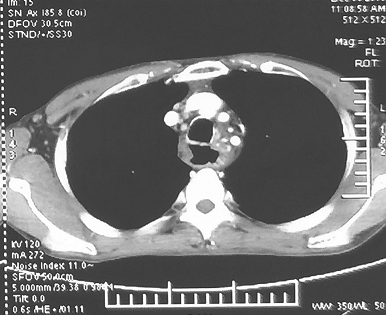

1小时条评论61岁女性,因确诊肺腺癌1年余,腹胀半个月入院,如何诊治? 【病例简介】 患者女性,61岁,因确诊肺腺癌1年余,腹胀半个月入院。患者于2015年7月出现乏力,无发热、咳嗽、咳痰、胸闷、胸痛和咯血。于外院体检行胸部CT检查发现左肺部占位伴胸腔积液。胸腔积液查见腺...